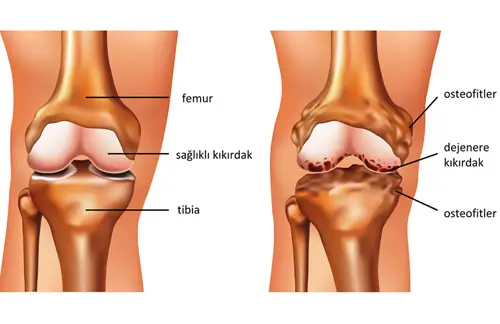

Kondromalazi Patella, diz kapağının (patella) altındaki kıkırdak dokusunun yumuşaması, incelmesi veya bozulması sonucu ortaya çıkan bir rahatsızlıktır. Halk arasında sıklıkla “koşucu dizi” olarak bilinir. Bu durum, özellikle genç yetişkinlerde, sporcularda ve fiziksel olarak aktif bireylerde sıkça görülür. Diz kapağının arkasındaki kıkırdak, normal şartlarda dizin hareketi sırasında femur kemiğiyle sorunsuz bir

Menisküs Yırtılması Nedir? Menisküs yırtılması, diz ekleminde yer alan kıkırdak benzeri yapının (menisküsün) zedelenmesi veya yırtılmasıyla oluşan bir ortopedik problemdir. Diz eklemi, uyluk (femur) ve kaval (tibia) kemikleri arasında yer alan iki adet menisküs sayesinde dengeli bir şekilde çalışır. Menisküsler, dizdeki yükün dengeli dağılmasını, şok emilimini ve eklemin stabilitesini sağlar.